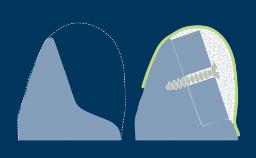

A osteotomia do implante é uma etapa cirúrgica essencial na implantodontia. Termina com a inserção de um implante dentário que posteriormente fornecerá ao paciente um substituto fixo ou removível para a ausência de dentes. Neste módulo, descreveremos primeiro a técnica correta de preparação óssea para a instalação do implante. Posteriormente, abordaremos os ajustes do protocolo necessários em diferentes densidades ósseas. Finalmente, discutiremos os riscos potenciais associados à técnicas inadequadas de osteotomia.

- selecionar o procedimento de perfuração apropriado para determinados tipos ósseos

- listar os efeitos das técnicas de perfuração e instrumentação inadequadas na estabilidade primária do implante e osseointegração